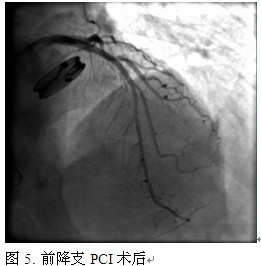

入院后立即给予拜阿司匹林、氯吡格雷抗血小板(负荷量)以及调脂、降压、扩管等对症治疗后,送往心导管室。经桡动脉途径行冠脉造影。检查提示:左主干未见明显狭窄,前降支中段狭窄90%,回旋支中段狭窄40%,右冠脉动脉粥样硬化(图1~3)。造影结束,送EBU3.5/GC至左冠脉口,将BWM指引导丝送至前降支远端,于前降支中段置入3.0*23mm药物洗脱支架一枚。重复造影:支架贴壁良好,未见明显残余狭窄,血流TIMI 3级(图4~5)。术中共使用肝素3500u。术后患者恢复良好,拜阿司匹林+氯吡格雷+华法林三联抗栓治疗6个月,之后拜阿司匹林+华法林维持到术后12个月,最后终身口服华法林治疗。